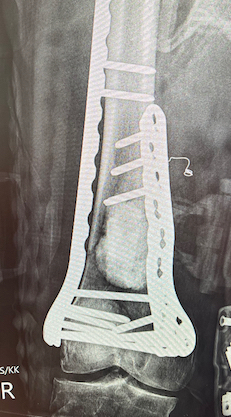

Dual plate

Indications

Significant comminution

Loss of medial cortical buttress

Approach

1. Dual incision

- medial + lateral approach

- midlateral approach - split ITB, elevate vastus lateralis

- medial subvastus approach

Technique

Results

- 21 comminuted distal femur fractures

- increased union rates with double v single plate

- increased revision rate with single plate